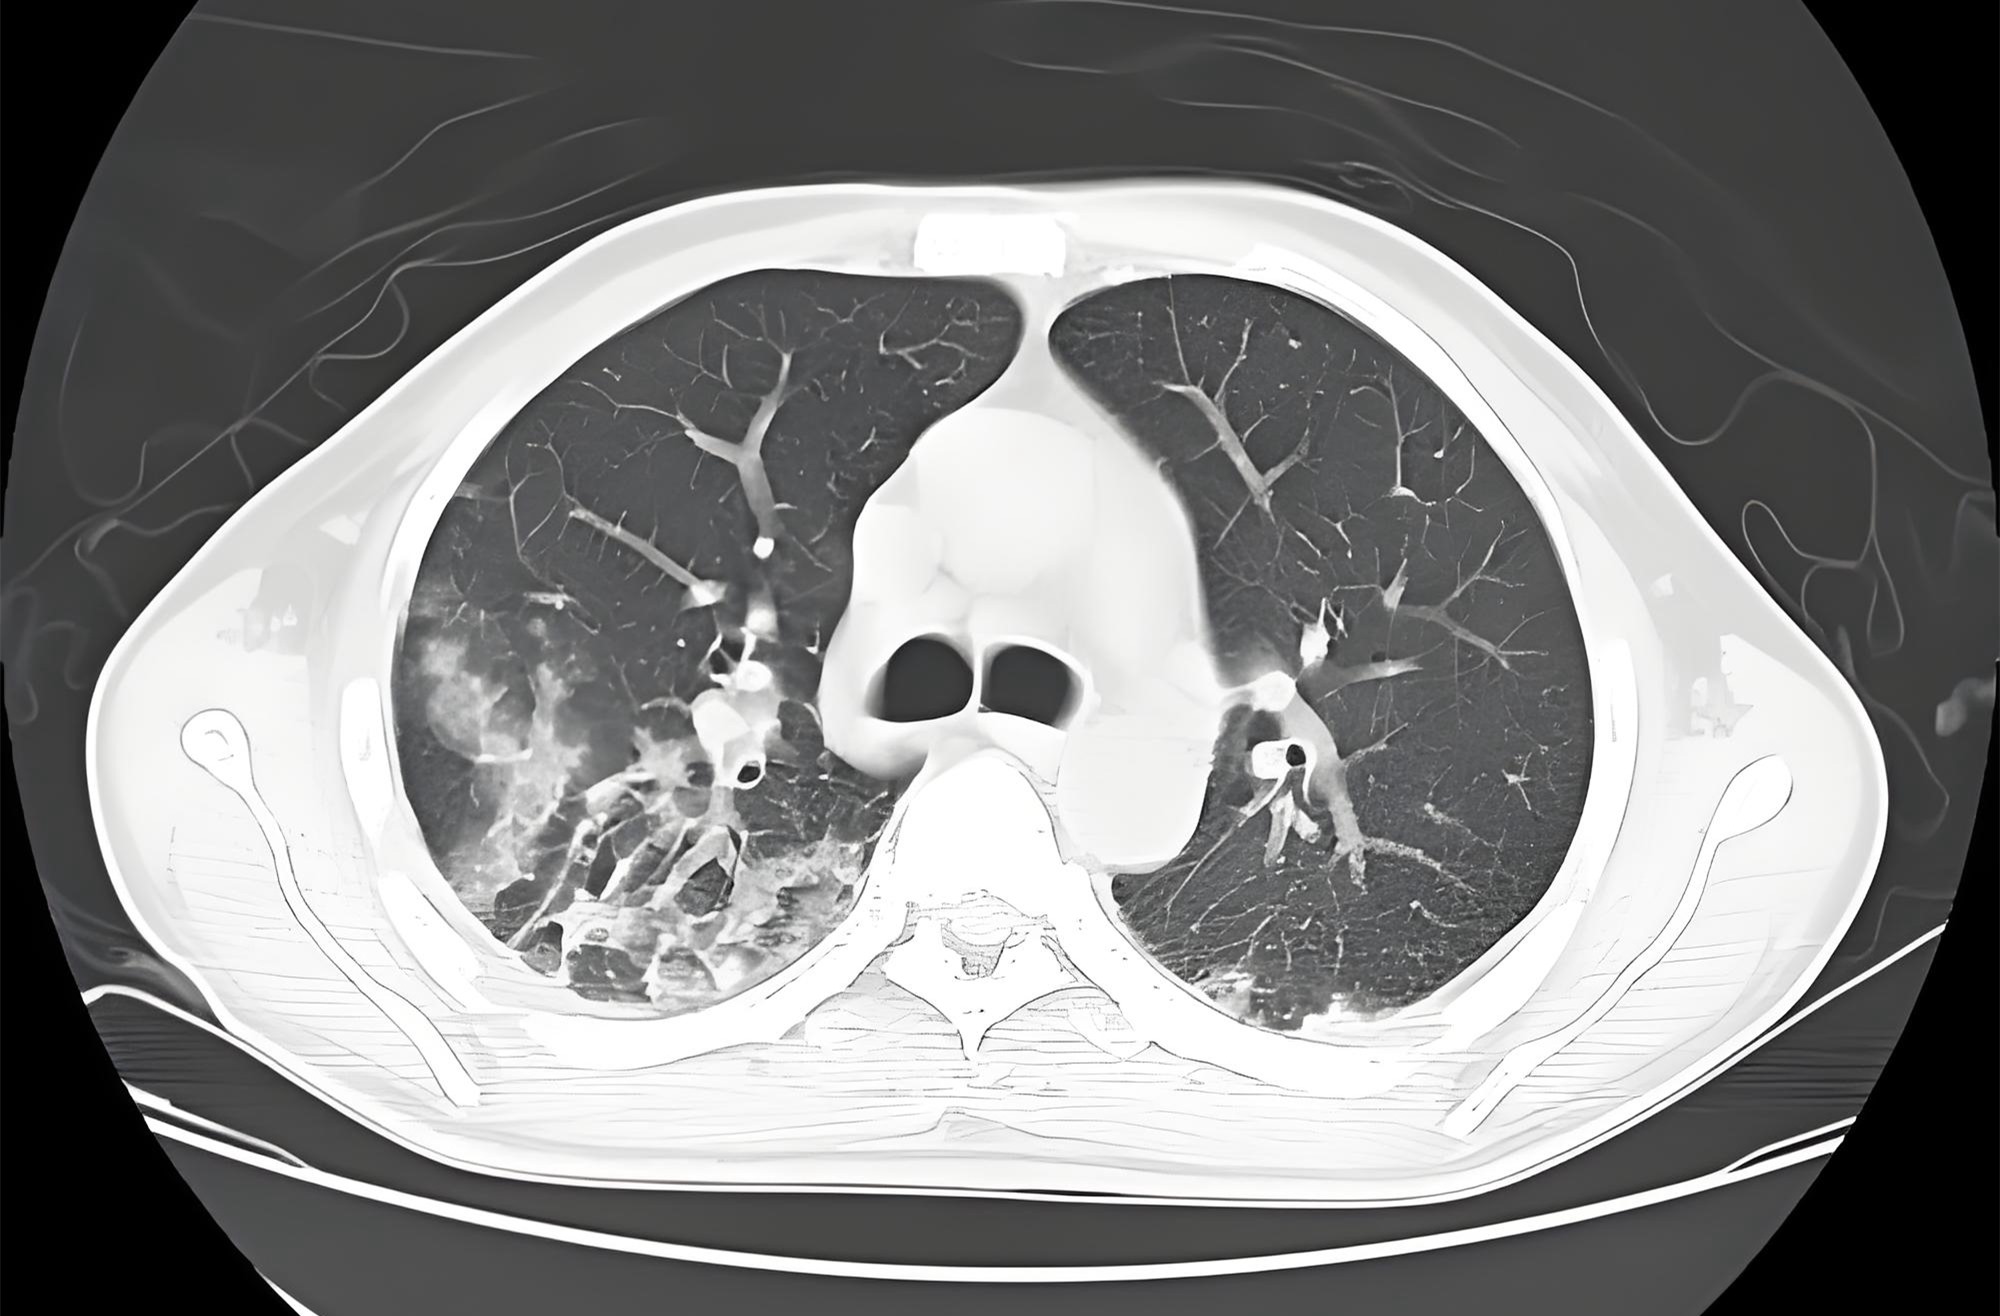

突发意识障碍,但无药物接触史,CT可见病灶